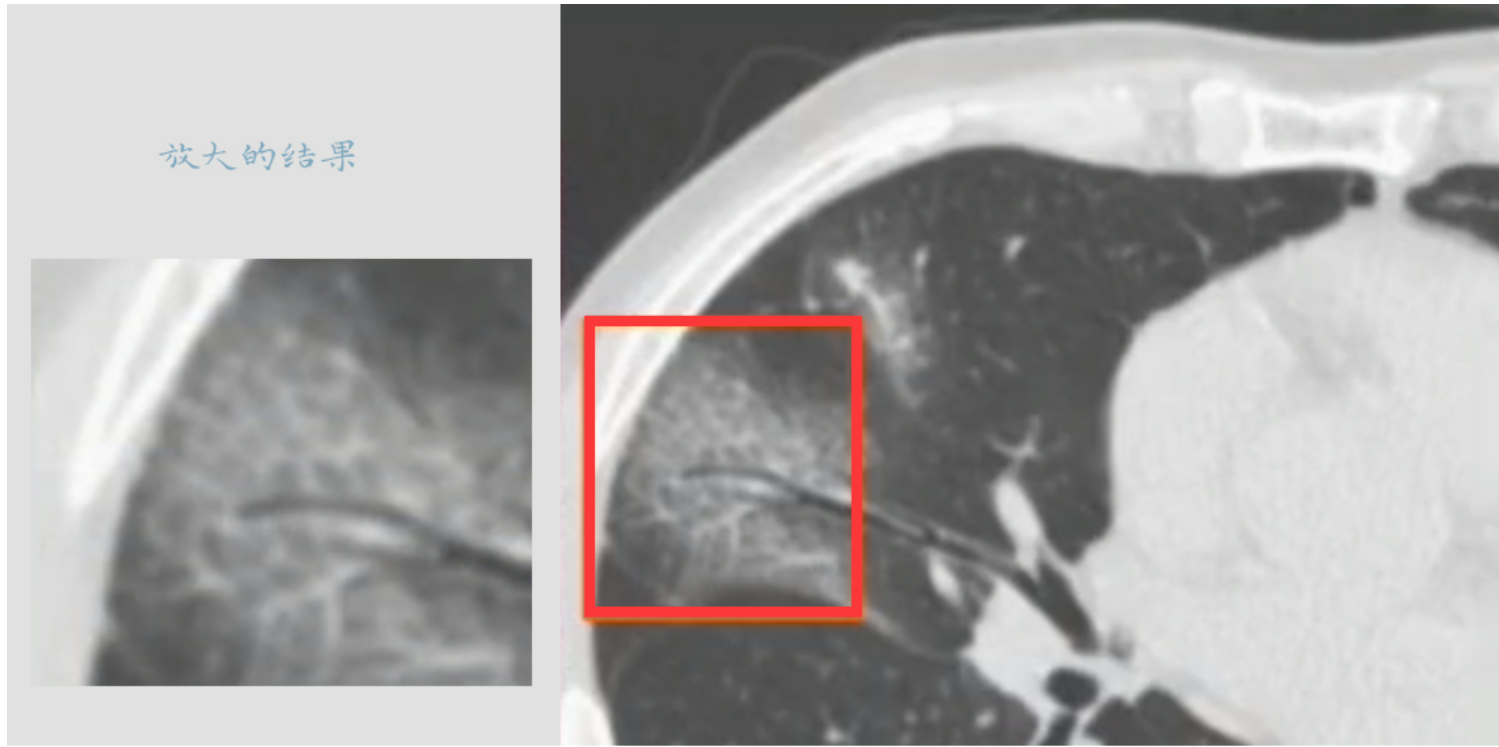

细小网格或者条状影

如果具备前两个特征,并且对磨玻璃影区域进行详细观察(源自广东省人民医院放射科行政副主任赵振军主讲《新型冠状病毒感染CT早期诊断和鉴别诊断》),则可能观察到如图所示的微小网格结构(来自上述报告)。这些发现通常反映在人读片时的观察中。然而,在机器识图的过程中又是如何依据哪些特征进行判断的呢?这个问题值得深入探讨。

图3.细小网格影